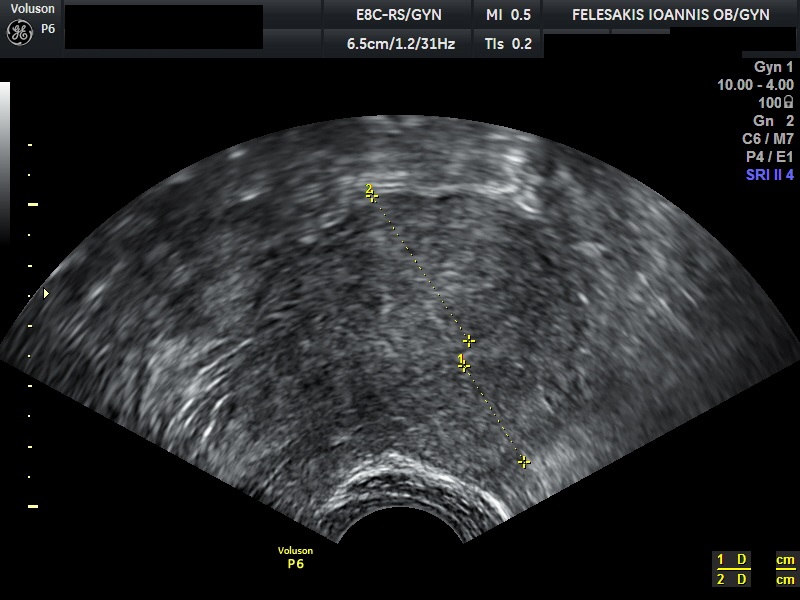

Τα συνηθέστερα συμπτώματα των γυναικών είναι η δυσμηνόρροια, η μηνορραγία και ο πόνος κατά την επαφή (δυσπαρεύνια). Σημαντικό είναι να τονιστεί, ότι η αδενομύωση δεν οδηγείται σε εξαλλαγή σε καρκίνο. Η διάγνωση της αδενομύωσης είναι δύσκολη, καθώς η υπερηχογραφική της εικόνα, πολλές φορές ομοιάζει με αυτή των ινομυωμάτων. Τη λύση έχει δώσει η Μαγνητική Τομογραφία (MRI) η οποία και βοηθάει στη διαφορική διάγνωση της υποκείμενης πάθησης.